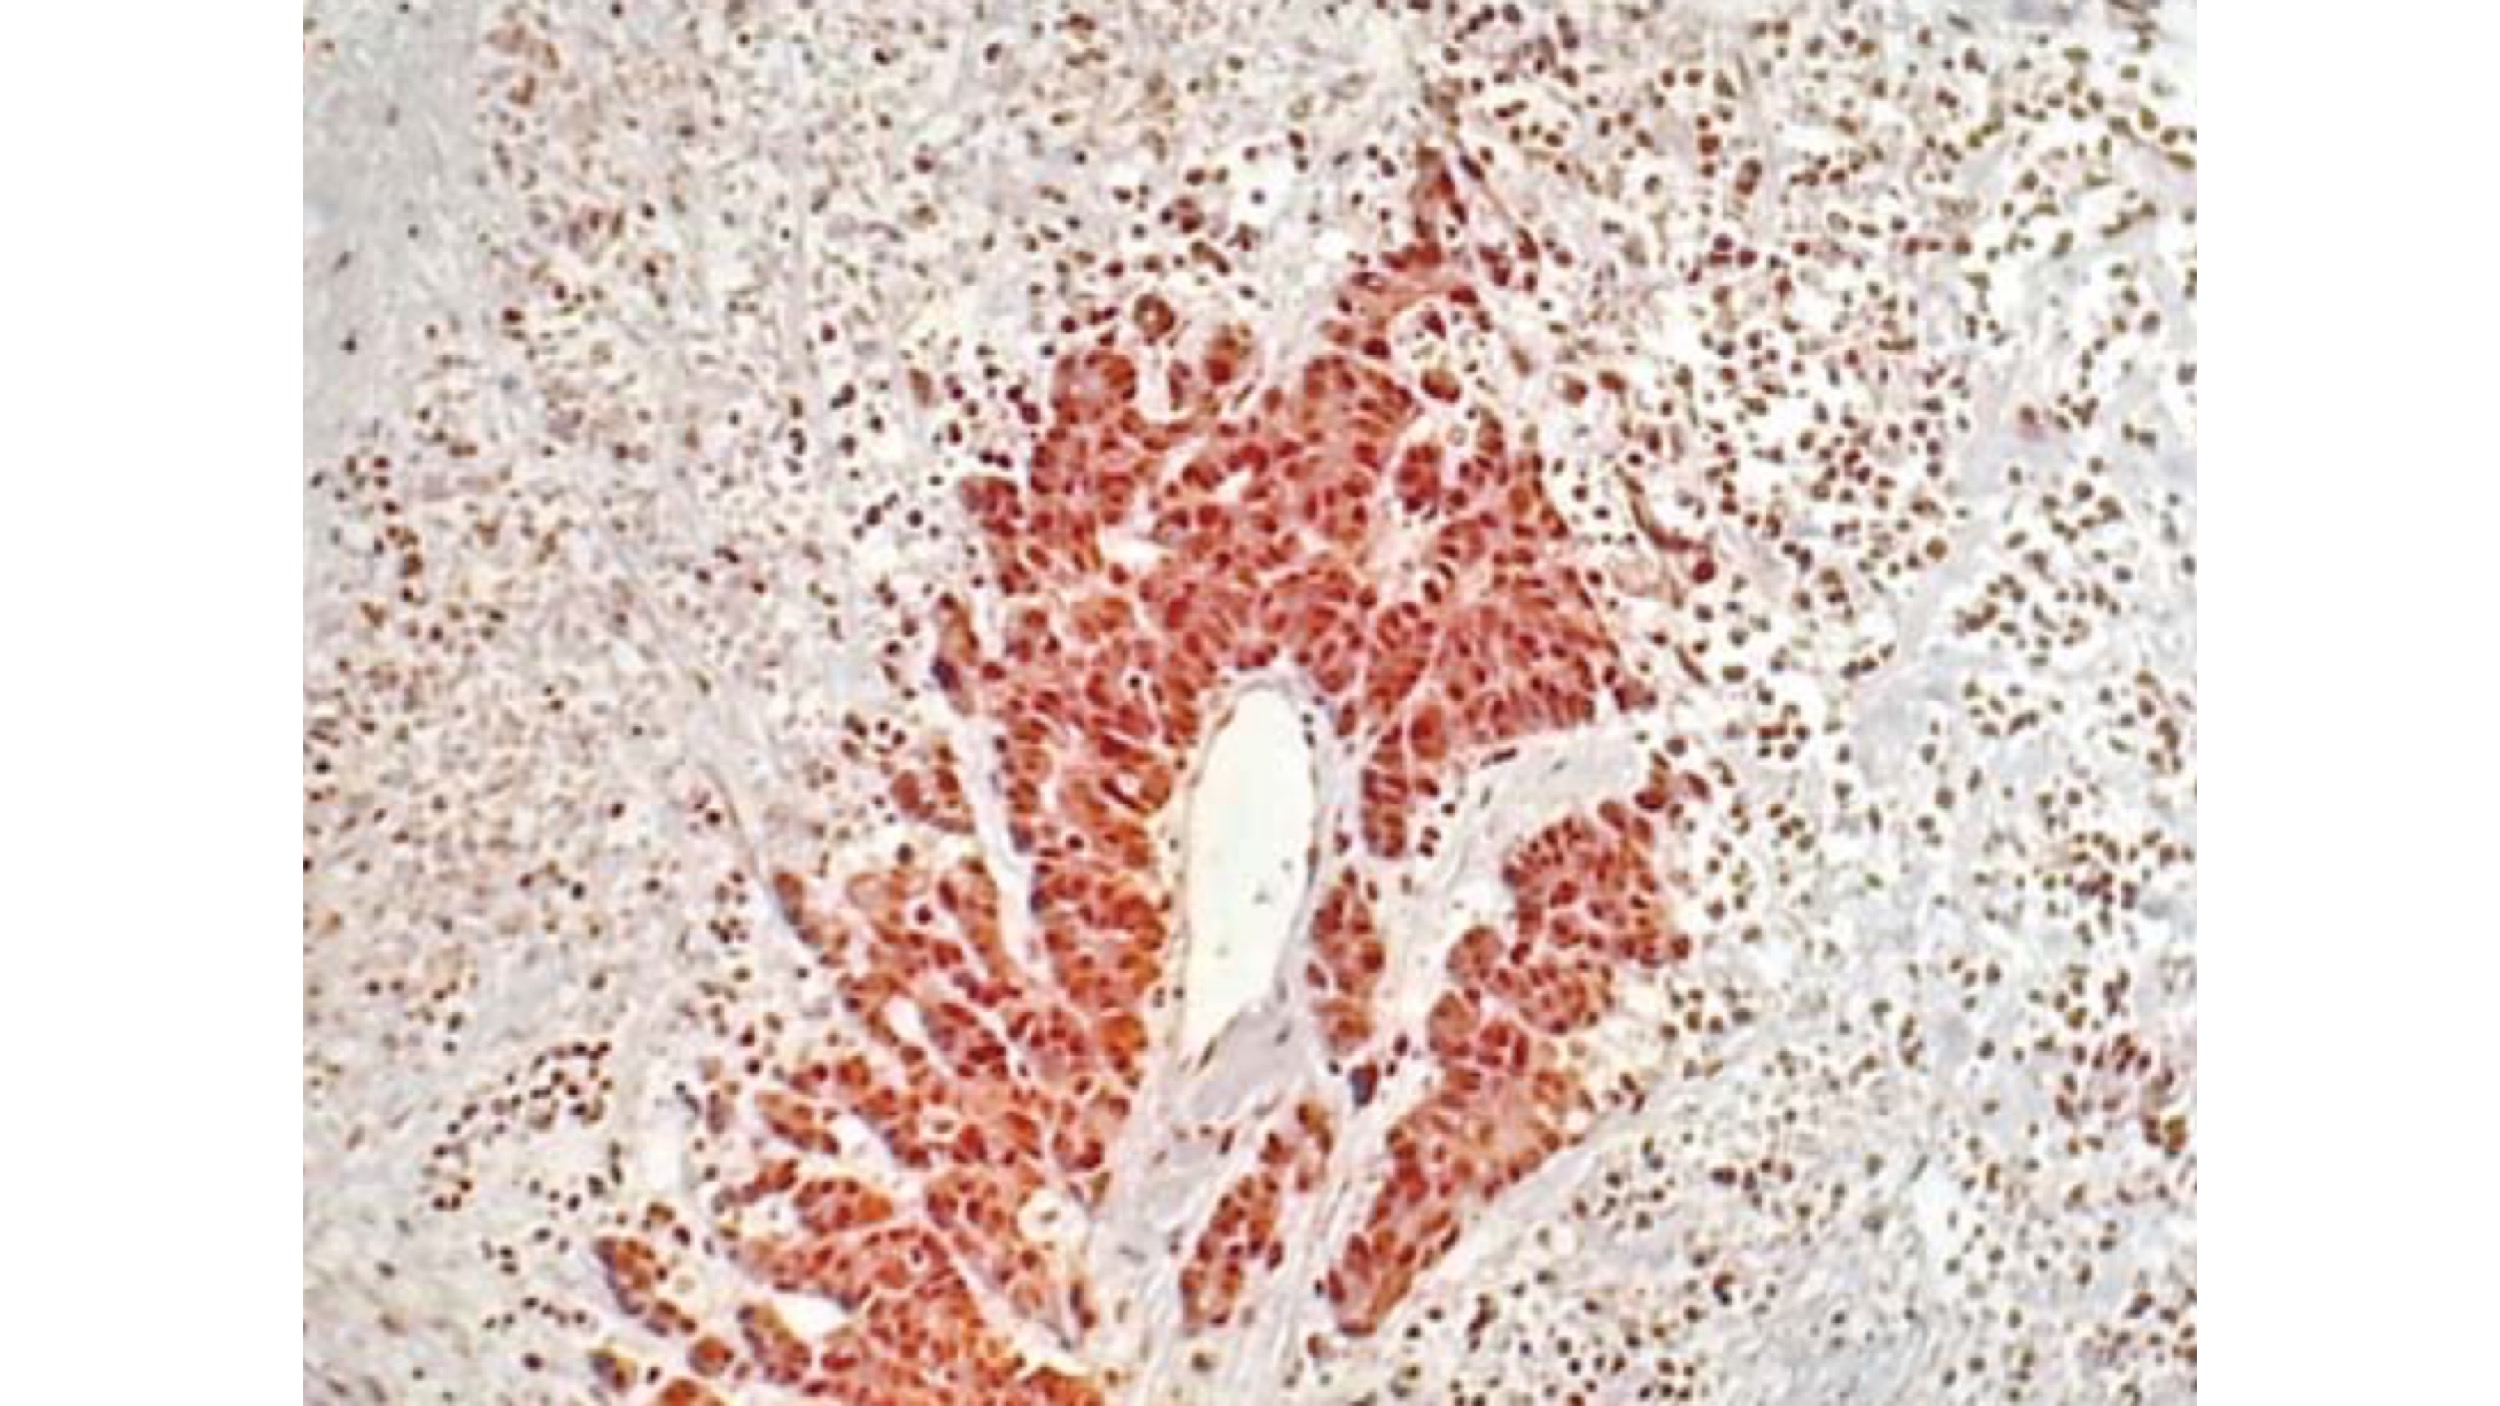

• Histology:

• Histopathology of leukoplakia can reveal a range of findings:

• Hyperkeratosis (orthokeratosis or parakeratosis) without dysplasia:

• The most common finding:

• Represents benign epithelial thickening

• Epithelial dysplasia:

• Classified as:

• Mild, moderate, or severe

• Characterized by:

• Architectural disturbance with blunt rete pegs, increased basal layer width, dyskeratosis (premature individual cell keratinization), nuclear enlargement, pleomorphism, hyperchromasia, and increased / atypical mitoses

• Carcinoma in situ or invasive squamous cell carcinoma:

• May be found on biopsy of clinically apparent leukoplakia

• Importantly, frank dysplasia is more frequently found in isolated (unifocal) leukoplakia than in PVL:

• Yet PVL has a much higher malignant transformation rate (~ 50% vs. ~ 9.5%), underscoring that histologic grade alone does not fully predict risk